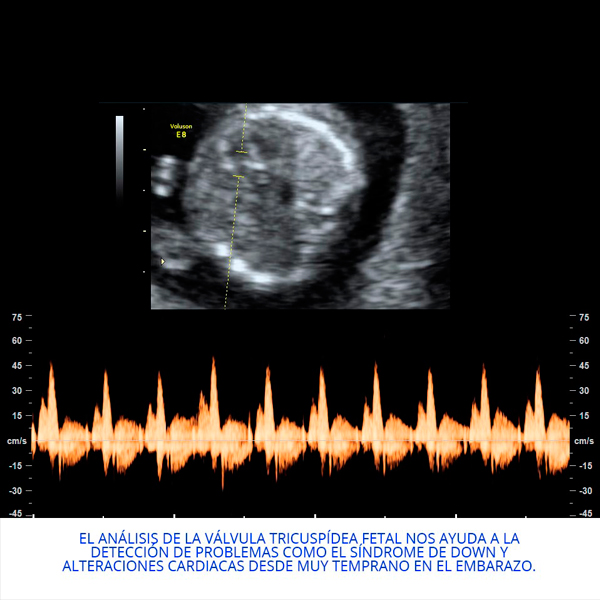

Actualmente realiza un Doctorado Internacional en Medicina Fetal avalado por las universidades de KU Leuven (Bélgica), Universidad de Barcelona (España) y la Universidad de Lund en Suecia, tres instituciones líder en el segmento de la medicina fetal a nivel mundial.